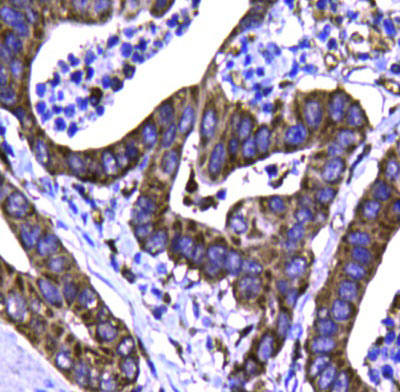

| Fig. 3. Immunohistochemical analysis of paraffin-embedded human gastric carcinoma tissue using anti-STAT6 antibody. Counter stained with hematoxylin. | Fig. 4. Flow cytometric analysis of Hela cells with STAT6 antibody at 1/100 dilution (blue) compared with an unlabeled control (cells without incubation with primary antibody; red).Goat anti rabbit IgG (FITC) was used as the secondary antibody |